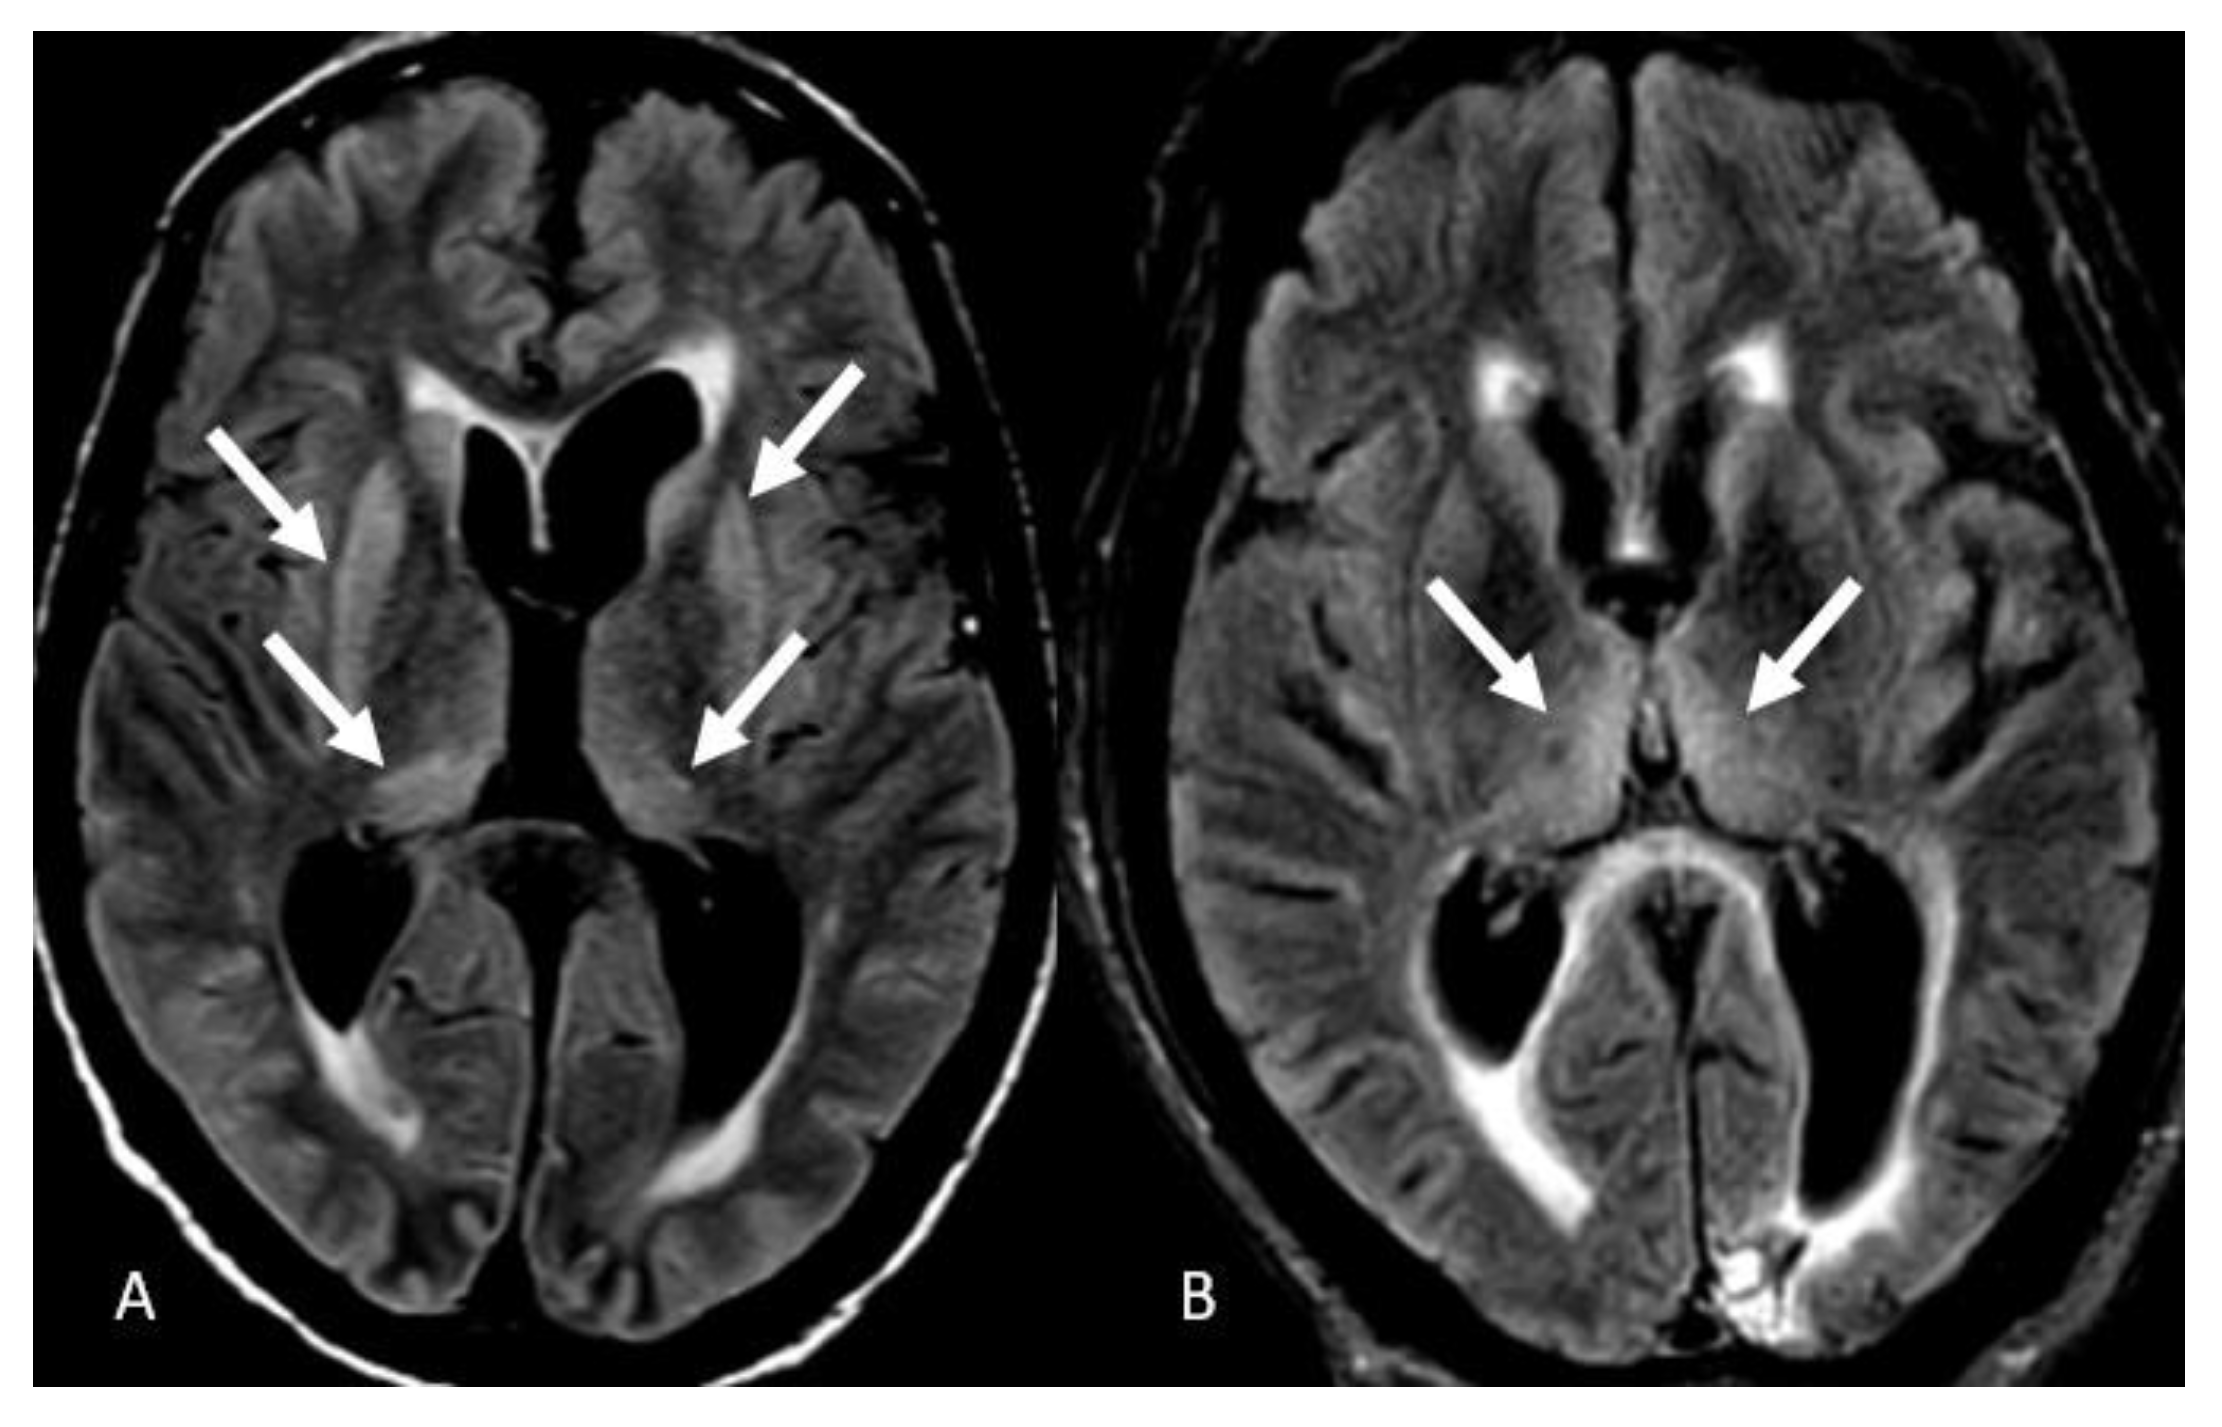

- Radmanesh, A.; Derman, A.; Lui, Y.W.; Raz, E.; Loh, J.P.; Hagiwara, M.; Borja, M.J.; Zan, E.; Fatterpekar, G.M. COVID-19-associated Diffuse Leukoencephalopathy and Microhemorrhages. Radiology 2020, 297, E223–E227. [Google Scholar] [CrossRef]

- Sharma, R.; Nalleballe, K.; Shah, V.; Haldal, S.; Spradley, T.; Hasan, L.; Mylavarapu, K.; Vyas, K.; Kumar, M.; Onteddu, S.; et al. Spectrum of Hemorrhagic Encephalitis in COVID-19 Patients: A Case Series and Review. Diagnostics 2022, 12, 924. [Google Scholar] [CrossRef]